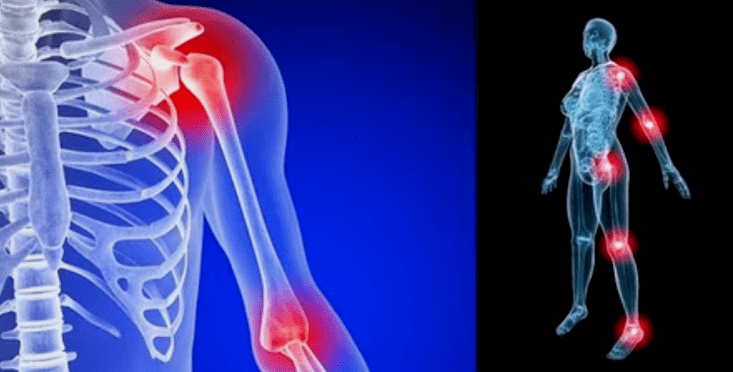

De manifestaties van de ziekte verschillen weinig, afhankelijk van de lokalisatie, vaker worden de tekenen weerspiegeld op de knieën, schouder- en heupgewrichten, vanwege een hoge belasting.

- pijn. Ze hebben een lage ernst in het beginstadium, met verergering van de sensatiestaat intensivering. Aanvankelijk kwamen de gewrichten alleen maar pijn na het wakker worden, na een lichte warme -up, verdwijnen de sensaties. Na verloop van tijd verschijnen de pijnen 's nachts, ze verstoren enorm tijdens en na langdurige wandelen, rennen, enz. In de laatste fase streeft het pijnsyndroom altijd een persoon;

- zwelling van roodheid. Het is gelokaliseerd in de buurt van het zieke gewricht, dit duidt op een ontstekingsproces en progressie van de ziekte. De arts begrijpt dat de synoviale schaal wordt beïnvloed, dit veroorzaakt de accumulatie van vloeistof en verhoogde pijn;